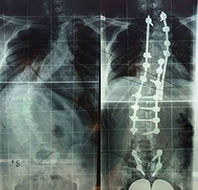

Műtét úgynevezett növekedő rendszerrel

Csigolyafejlődési rendelenesség - röntgen Jellemzően már a nagyobb mértékű gerincferdülés kialakulásánál dönthet a gerincsebész ún. növekedő rendszeres műtéti kezelésről. Ezt a még növekedésben lévő gyermekeknél, tehát a csontérettség (pubertás) előtt alkalmazzák, és műtétek sorát jelenti. A módszer bravúrosnak tekinthető, hiszen egyszerre biztosítja a gerinc növekedését és a görbület korrigálását. Mivel több beavatkozásról van szó, mindenképp megterhelő, de ugyanúgy gyors felépüléssel, és teljes élet lehetőségével jár a gyermekek számára.